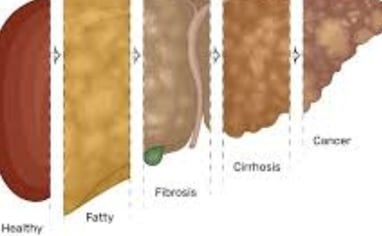

مرض الكبد الدهني، المعروف أيضًا باسم مرض الكبد الدهني غير الكحولي (NAFLD)، يتضمن تراكم الدهون الزائدة في الكبد.

يمكن أن يحدث تلف خطير في الكبد، مما يؤدي إلى حالات مثل التشمع وحتى السرطان.

هناك نوعان رئيسيان من الكبد الدهني: مرض الكبد الدهني غير الكحولي (NAFLD) الذي يتضمن تراكم الدهون في الكبد، ومرض التهاب الكبد الدهني غير الكحولي (NASH) الذي يترافق مع علامات الالتهاب وتلف خلايا الكبد.

التهاب الكبد: يبدأ من حالة دهون إلى حالة ملتهبة (متورمة).

التليف: يتكون نسيج ندبي نتيجة الالتهاب الذي يؤدي إلى تلف الكبد.

تليف الكبد: حيث يتم استبدال الأنسجة السليمة بنسيج ندبي.

سرطان الكبد: يمكن أن يتطور نتيجة لهذه الحالات.

الكبد الدهني من الدرجة الأولى: يعتبر حالة خفيفة حيث تشكل الدهون 5-10% من الكبد. من المهم تناول طعام صحي وممارسة الرياضة بانتظام.

الكبد الدهني من الدرجة الثانية: يحدث عندما تتراوح نسبة الدهون في الكبد بين 10-25%.

الكبد الدهني من الدرجة الثالثة: هو الأكثر خطورة، حيث يشير إلى نسبة مرتفعة من الدهون في الكبد مع التهاب في الأنسجة المحيطة.